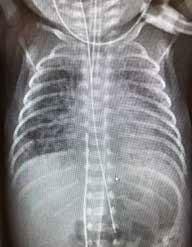

Fysiologi og hemodynamikk I de første minuttene etter fødselen skjer det store fysiologiske endringer i barnets respirasjon og sirkulasjon. Lungene tar over som gassutvekslingsorgan, og den vaskulære mostanden i lungearteriene synker som følge av økt oksygenkonsentrasjon. Når lungekarmotstanden faller, fylles lungene med blod som deretter strømmer via lungevenene tilbake til venstre hjerte halvdel (Fig.1). Dette sikrer god fylning (preload) til venstre ventrikkel som kan opprettholde et tilstrekkelig slagvolum. Slik unngår barnet store blodtrykksendringer (1, 2)

Dersom barnets lunger ikke fylles med luft, forblir lungekar motstanden høy, og det går lite blod til lungene. Avklemming av navlesnoren i denne situasjonen vil kutte blodforsyningen til barnet via navlevenen, og venstre ventrikkel får redusert fylning (preload), fordi manglende venøs retur fra placenta ikke kompenseres av økt venøs retur fra lungevenene. I tillegg øker motstanden i systemkretsløpet (afterload) på grunn av at navlearteriene er avklemt. Dette kan føre til kardiovaskulær instabilitet i de første, viktige minuttene av barnets liv og forstyrre transisjonsprosessen.

Intakt navlesnor inntil barnet har etablert pulmonal gassutveksling, gir mer stabil hemodynamikk med potensielt store gevinster, blant annet redusert risiko for hjerneblødning. Så lenge navlesnoren er intakt, kan noe gassutveksling fortsatt foregå gjennom placenta og beskytte mot asfyksi, selv om barnet er utenfor uterus.

Figuren viser mekanismer for ustabil hemodynamikk ved tidlig avnavling. Modifisert fra referanse 2, Uwins et al, med tillatelse.